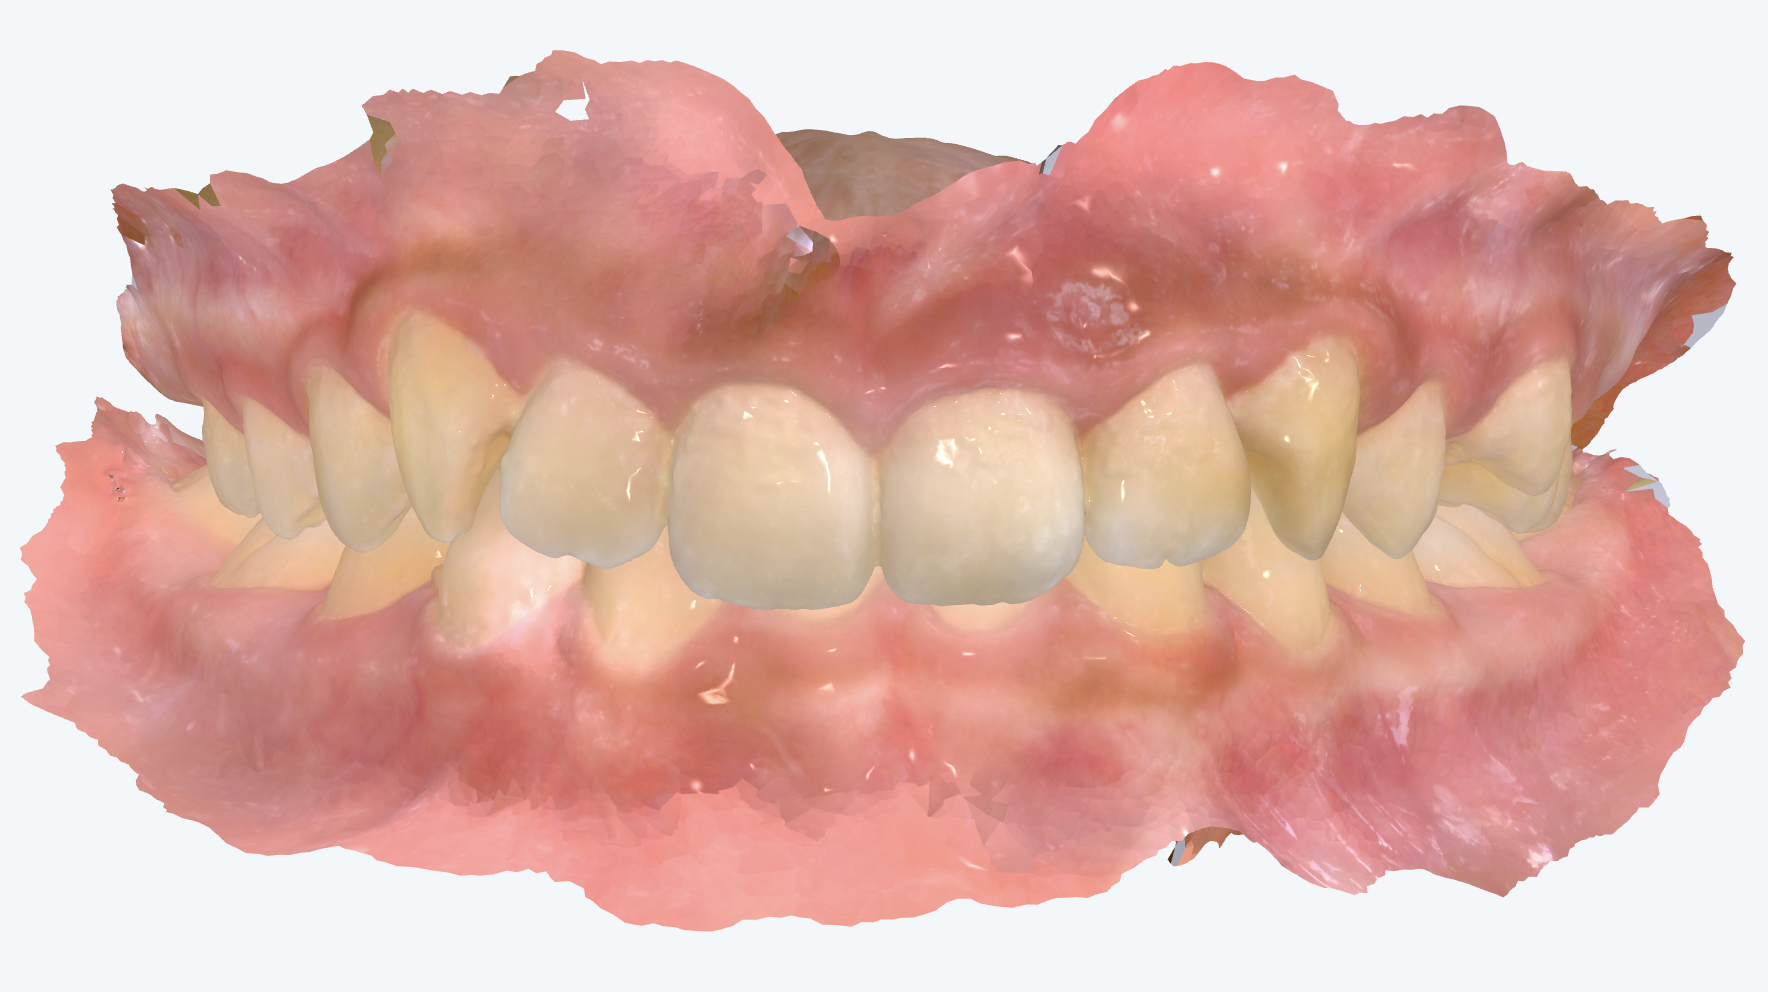

初診時の画像診断

上の前歯が後方に傾くことで前歯が噛んでいます。前歯が後方に傾くことで噛み合わせが深くなっています。

下の左右の前から2番目の歯がもともとありません(先天欠如)。